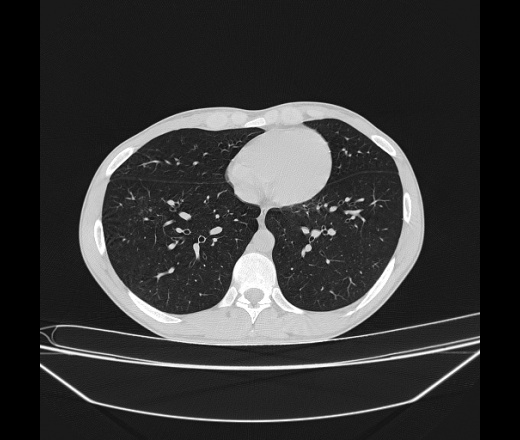

Молодой парень 18 лет, призывник, при прохождении ФЛС на верхушек левого легкого выявили очаги средней интснисвности с нечеткими контурами, тяжи. Сделали бок и томограммы 6-7-8. Везде описывают как очаговый твс. Вижу только перибронхиальный фиброз. Что за изменения в бронхах, указано нижи стрелками, тоже перибронхиальный?